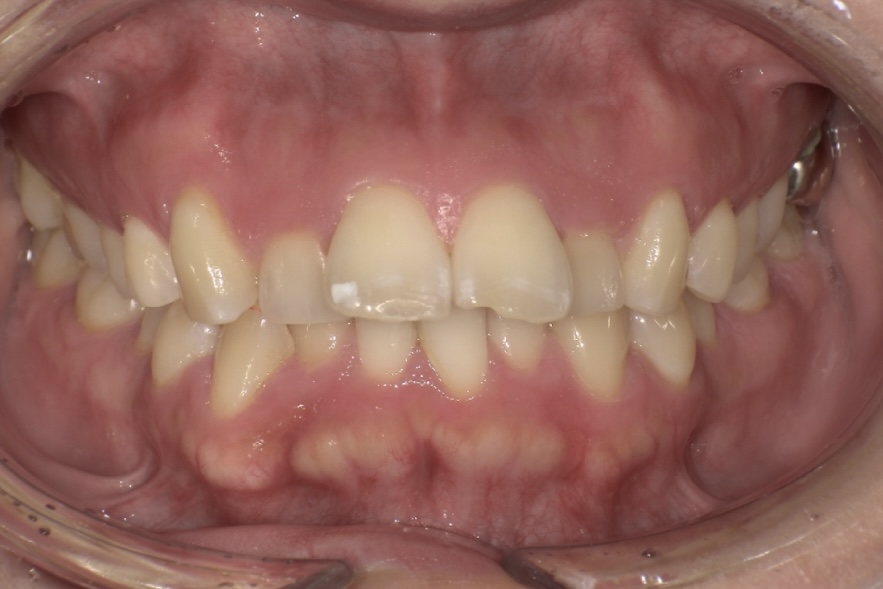

今回の症例の患者さまは30代女性で、出っ歯、下の前歯のガタつき、前歯で噛めないことを主訴にご来院されました。

見た目の改善に加え、長年前歯で噛むことができず、常に奥歯で食事をしている点も気にされていました。

診断の結果、上顎前歯の唇側傾斜が強く、歯並びの状態だけを見ると抜歯を検討するケースでしたが、患者さまの「できるだけ抜歯は避けたい」というご希望を踏まえ、奥歯の遠心移動とIPR(歯と歯の間をわずかに調整する処置)を適切に組み合わせることで、抜歯を行わずに治療を進めました。

その結果、前歯の突出感や下の前歯のガタつきが改善し、前歯でしっかり噛める機能的な咬み合わせを獲得することができ、見た目と機能の両面で良好な結果が得られた症例です。

BEFORE